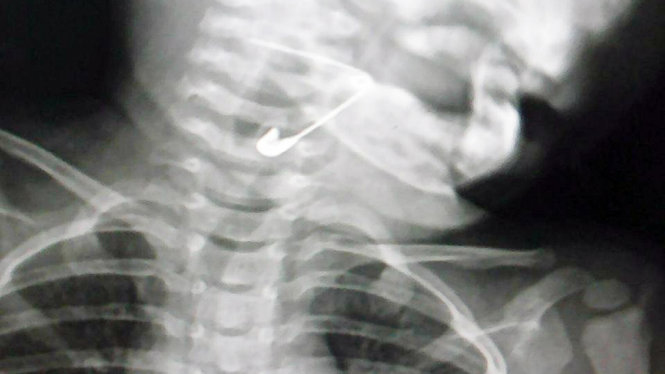

Kim băng trong thực quản bé gái 18 tháng tuổi - Ảnh: BT.

“Kết quả, chúng tôi phát hiện cây kim băng nằm trong thực quản của cháu bé. Ngay lập tức, tôi đã nội soi họng của cháu và gắp cây kim băng ra ngoài. Nếu kim băng rơi vào thanh quản thì sẽ rất nguy hiểm”, bác sĩ Phương cho biết thêm.